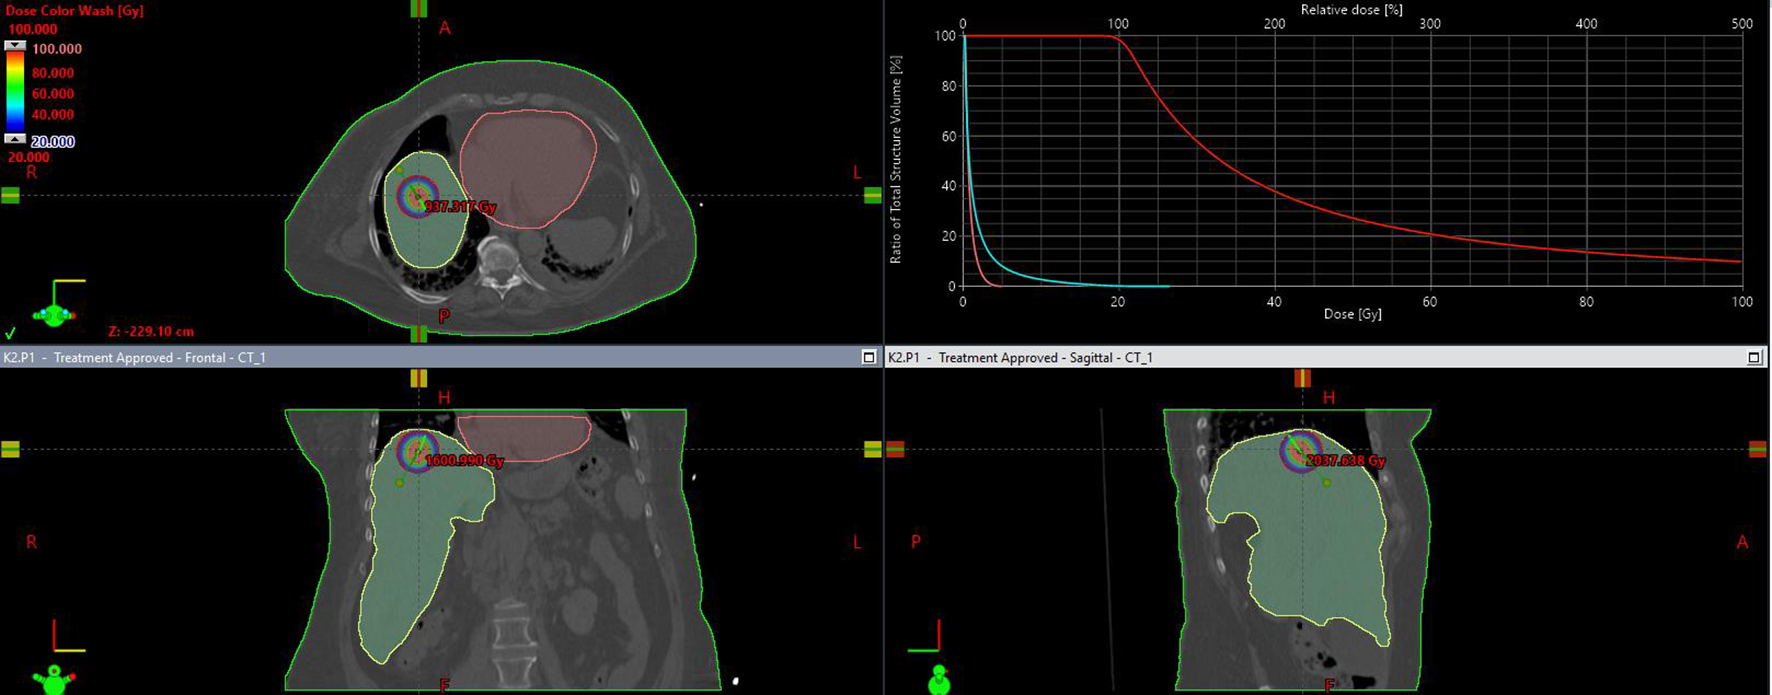

Patients were qualified based on their general condition, the results of current imaging and laboratory tests, the current stage of advancement, response to previous systemic treatment and the possibility of obtaining local control. 298 applications were performed. In most patients (252), applications were performed during a single procedure. The remaining patients, who required more than 4–5 applicators or had more than 3 metastases in different segments of the liver, undervent two application procedures. The application procedure was performed under general anaesthesia or local infiltration anaesthesia combined with sedation or conduction anaesthesia (intercostal block) combined with sedation. First, CT scanning with or without contrast was performed in layers at 2 mm intervals to localise the metastasis. For this purpose a 32-slice tomograph on rails with real-time fluoroscopic imaging (Somatom Siemens Germany) was used. If necessary, the CT scan was combined with other earlier imaging tests performed (MRI, PET CT). Under the control of continuous fluoroscopic CT imaging, the intercostal space was located through which access to the metastasis was as convenient as possible, i.e. it avoided large blood vessels, intestinal loops, stomach, pleura and pericardial sac. The application was carried out on the upper edge of the rib to avoid the costovascular bundle running along the lower edge of the rib. Flexible needles measuring 200 mm or 320 mm in lengh (Varian, USA) were used for application. The applicators were placed within the lesion in accordance with the Paris system rules, parallel to each other, so that the end of the applicators were positioned in the distal pole of the metastasis (due to the so-called “dead end” of the applicator, amounting to 4 mm) (Figure 1 After the applicators were placed in the optimal position, treatment planning tomography was performed and used to inform the treatment plan. Three dose ranges (15 Gy, 20 Gy and 25 Gy) were used, depending on lesion size, doses to critical structures and treatment intention. The optimal dose distribution was considered if the specified dose was administered at a level of at least 95% of the isodose (D95), and an acceptable dose distribution was considered if the specified dose was administered at a level of at least 90% of the isodose (D90) (Figure 2). The main critical organ was the liver (D tolerance = D2/3 < 5Gy), as well as the stomach (D tolerance = D1cm3<15Gy), gall bladder (D tolerance = D1cm 3 max<20 Gy), intestines (D tolerance = D1cm3<12Gy), kidney (V7Gy<2/3 volume).

Figure 2

Isodose distribution on transverse, frontal, saggital plane and dose volume distribution histogram.

Treatment planning was performed in the Brachyvision ver. 10–12 treatment planning system (Varian USA). The treatment used a 24-channel device for remote charging of Gammamed sources (Varian USA) equipped with an Ir192 source with an average activity of 10 Ci and a diameter of 0.6 mm.